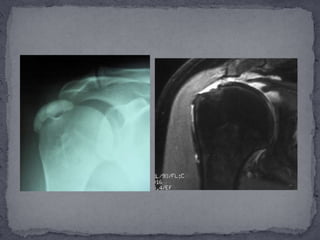

radiografías simples en casos agudos debe ser reservada para los pacientes con antecedente de trauma y sospecha de fractura o luxación. También en y procesos articulares avanzados. Se ha mostrado que las radiografías simples tienen la habilidad de mostrar la relación entre los segmentos del húmero proximal y la articulación Glenohumeral. Acromion.PARACLÍNICOS

Las imágenes de resonancia magnética permiten una completa evaluación del hombro. Con esta modalidad de imágenes, es ahora posible diagnosticar enfermedad del manguito, desde una simple tendinosis hasta una ruptura completa, así como rupturas intratendinosas o rupturas en el aspecto bursal del tendón.Las imágenes de resonancia magnética han demostrado 100% de sensibilidad y 95% de especificidad en el diagnóstico de rupturas completas, y predice consistentemente el tamaño del desgarro del tendón. La atrofia del músculo supraespinatus se correlaciona con el tamaño de unacompleta y crónica ruptura del tendón. La sensibilidad y especificidad en la diferenciación de tendinitis de la degeneración del tendón en un 82 a 85% y la diferenciación de un tendón normal de uno afectado por tendinitis con signos de pinzamiento con sensibilidad y 80 especificidad del 93% y 87% respectivamente.

radiografías simples encasos agudos debe ser reservada para los pacientes con antecedente de trauma y sospecha de fractura o luxación. También en y procesos articulares avanzados. Se ha mostrado que las radiografías simples tienen la habilidad de mostrar la relación entre los segmentos del húmero proximal y la articulación Glenohumeral. Acromion.PARACLÍNICOS

Las imágenes deresonancia magnética permiten una completa evaluación del hombro. Con esta modalidad de imágenes, es ahora posible diagnosticar enfermedad del manguito, desde una simple tendinosis hasta una ruptura completa, así como rupturas intratendinosas o rupturas en el aspecto bursal del tendón.Las imágenes de resonancia magnética han demostrado 100% de sensibilidad y 95% de especificidad en el diagnóstico de rupturas completas, y predice consistentemente el tamaño del desgarro del tendón. La atrofia del músculo supraespinatus se correlaciona con el tamaño de unacompleta y crónica ruptura del tendón. La sensibilidad y especificidad en la diferenciación de tendinitis de la degeneración del tendón en un 82 a 85% y la diferenciación de un tendón normal de uno afectado por tendinitis con signos de pinzamiento con sensibilidad y 80 especificidad del 93% y 87% respectivamente.